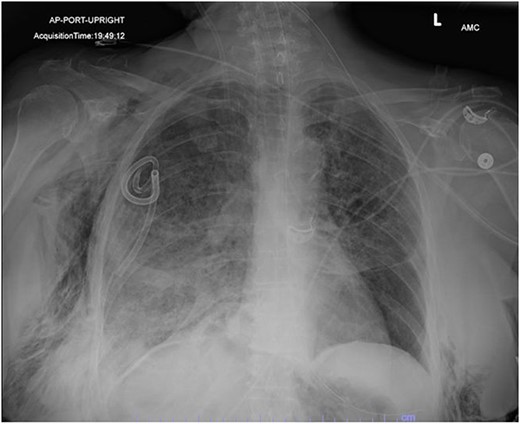

In the operating room (OR), the patient underwent intubation for TBNA using the Monarch® robotic bronchoscopy platform. Nine needle aspirations were obtained from the third-order RLL bronchi with each aliquot subjected to rapid on-site examination. While awaiting results, the patient developed retching, hemoptysis, bronchial bleeding from the superior segment of the RLL lobe and hypotension. The bleeding was managed with ice-cold saline and epinephrine. The patient required aggressive resuscitation with crystalloid, blood products and vasopressor therapy. She was transferred to the ICU where she remained intubated for ongoing resuscitation. In the ICU, the patient developed recurrent hypotension. Chest X-ray (CXR) revealed a right-sided pneumothorax (Fig. 1) that was treated with a small-bore pigtail chest tube and resulted in immediate improvement of her tension physiology. The pneumothorax resolved on repeat chest film while the patient remained intubated and sedated (Fig. 2).